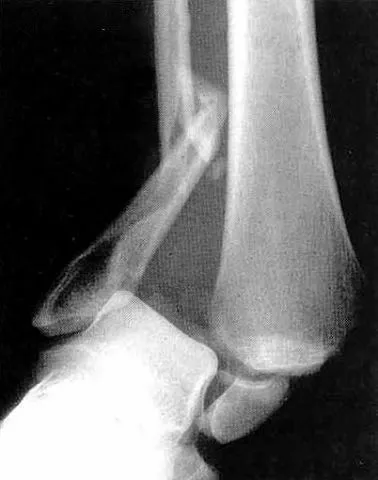

The ankle has two joints, one on top of the other, and three bones. A broken ankle can involve one or more of the bones, as well as injury to the surrounding connecting tissues or ligaments.

The treatment for a broken ankle usually involves a leg cast or brace if the fracture is stable. If the ligaments are also torn, or if the fracture created a loose fragment of bone that could irritate the joint, surgery may be required to secure the bones in place so they will heal properly.